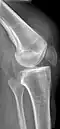

Quadriceps tendon rupture in plain X-ray: Incomplete rupture with haematoma in tendon. -